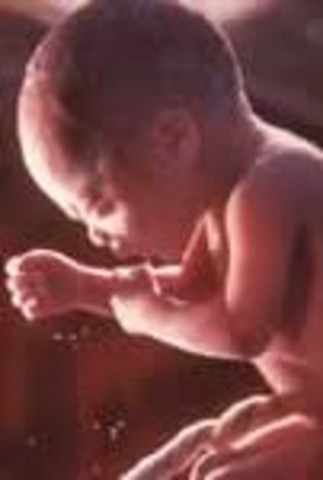

• week 32

week 32

Fat layer under skin is getting thicker.Baby is 17 inches long and for pounds.